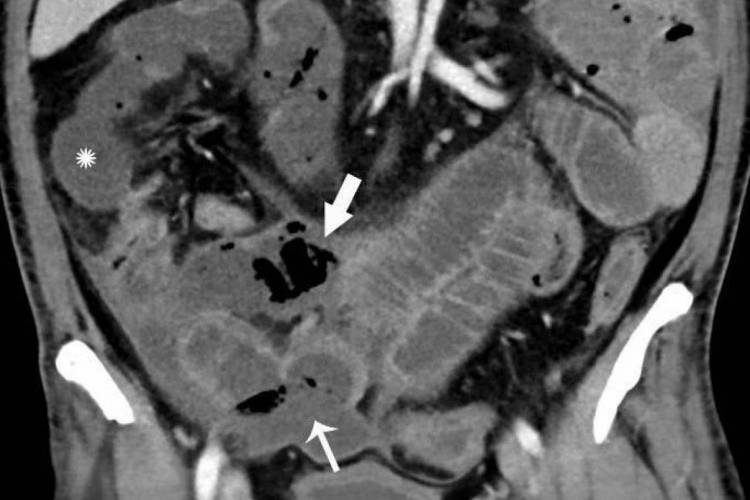

Foto 1: Tomografia de um homem de 57 anos com alta suspeita clínica de isquemia intestinal (Foto: Divulgação/Radiological Society of North America)

Foto 2: Homem de 47 anos de idade com sensibilidade abdominal apresenta características de isquemia e infarto mesentérico (Foto: Divulgação/Radiological Society of North America)

Foto 3: Homem de 54 anos demonstra pneumatose cistoide intestinal (setas) em um segmento longo do íleo. (Foto: Divulgação/Radiological Society of North America)